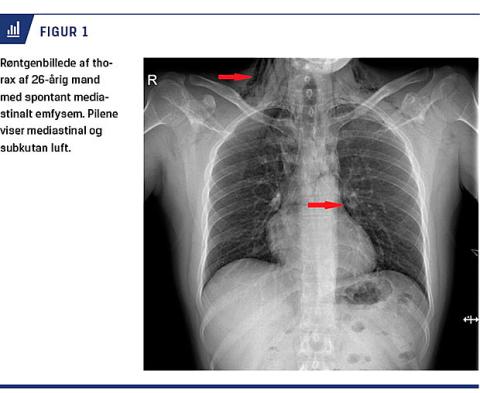

Hos børn er eleveret thymus et klassisk tegn. Hvis røntgenbilledet viser normale forhold, men der fortsat er klinisk mistanke om intratorakal patologi, anbefales CT af thorax. Her kan Macklineffekten, som defineres som ansamling af luft i den bronkovaskulære hinde og det omkringliggende væv, ses hos 100% af patienterne med SME. Hyppigst ses luften i hilusområdet, men hos halvdelen af patienterne kan den også ses længere perifert [1, 7, 13]. På CT visualiseres desuden eventuel luft i perikardiet, retroperitoneum, peritoneum og spinalkanalen) (Figur 2 og 3)[5].